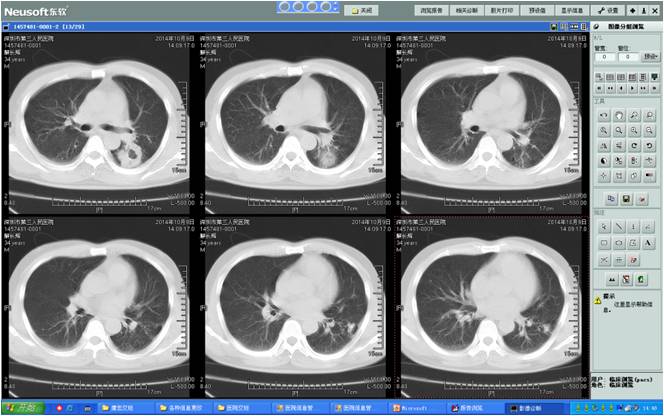

术前胸部CT